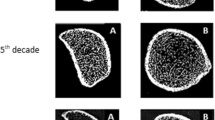

Representative 3D images of the distal radius and tibia for each age group are shown in Fig. 1.